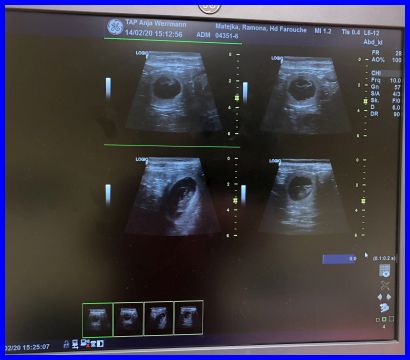

Ultraschallbilder

Theoretisch könnten das vier Babys sein...

Da ist es, das erste Baby, man kann es ganz deutlich in der Fruchtblase sehen.

Farouche ist tragend, wir erwarten die Babys um den 18.03.2020 und freuen uns schon alle riesig! Ab sofort nehme ich Vorbestellungen für die Babys an.